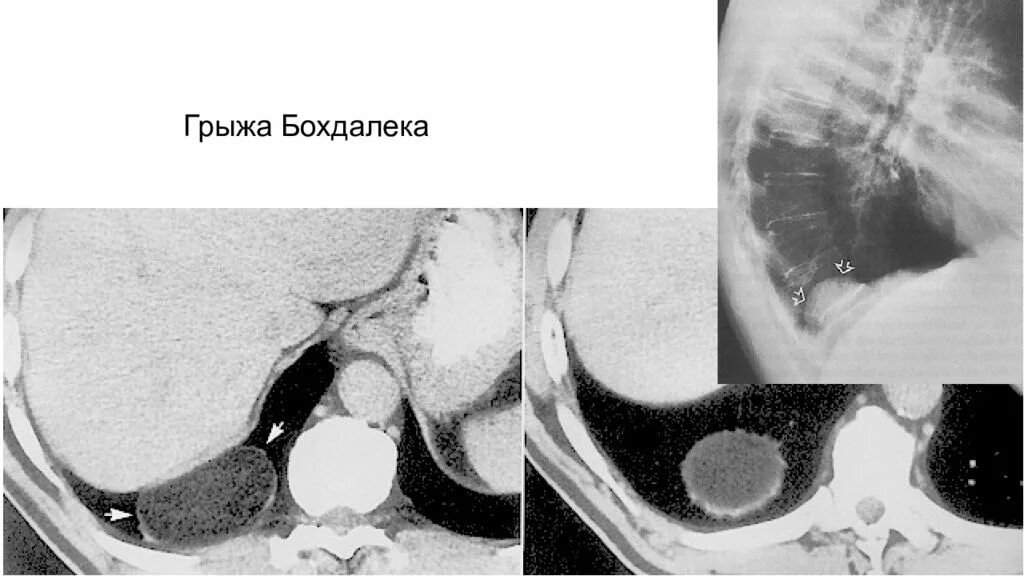

Грыжи на кт